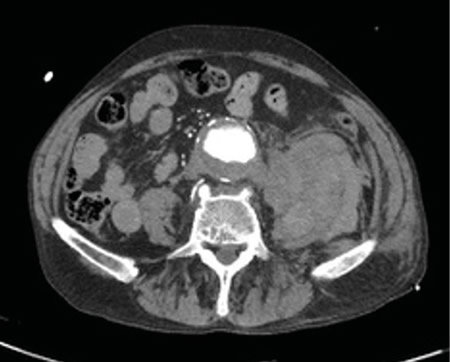

La rotura de aneurisma de aorta supone el síntoma principal en hasta un 25 % de los casos de la patología de aneurisma de aorta, que constituye una entidad potencialmente mortal. También puede aparecer con menor prevalencia como lumbalgia, coxalgia e, incluso, gonalgia, no comentándolo como dolor vertebral o neuropático, sino como irritación a nivel de psoas ilíaco como primera sintomatología.

Se estima que solo en un 50 % de los casos aparece la triada clásica del aneurisma, por lo que es necesario tener un alto nivel de alerta para sospecharlo, ya que la hipovolemia puede estar contenida por un hematoma peritoneal.

Figura 2